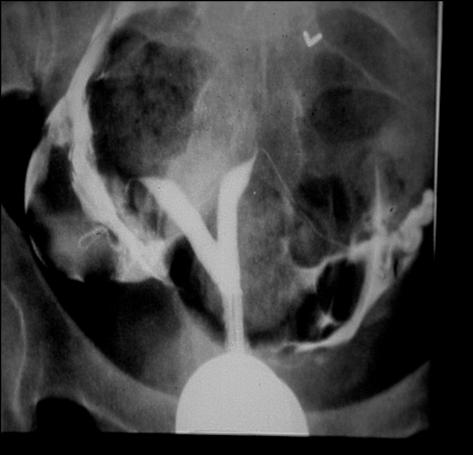

Hysterosalpingogram (HSG) • Assess uterine cavity for shape and filling defects • Check for tubal patency Hysterosalpingogram (HSG) • Performed in the follicular phase • Absolute contraindications: pregnancy, pelvic infection, allergy to iodine – Pregnancy test should be done prior to x-ray • Risk of infection following HSG in those patients with confirmed distally blocked tubes • Prophylactic antibiotics should be given to women with

Assessing Tubal

What is the Diagnosis? Lesser - Infertility Work-up 63

Patency Normal HSG Tubal Obstruction HSG: